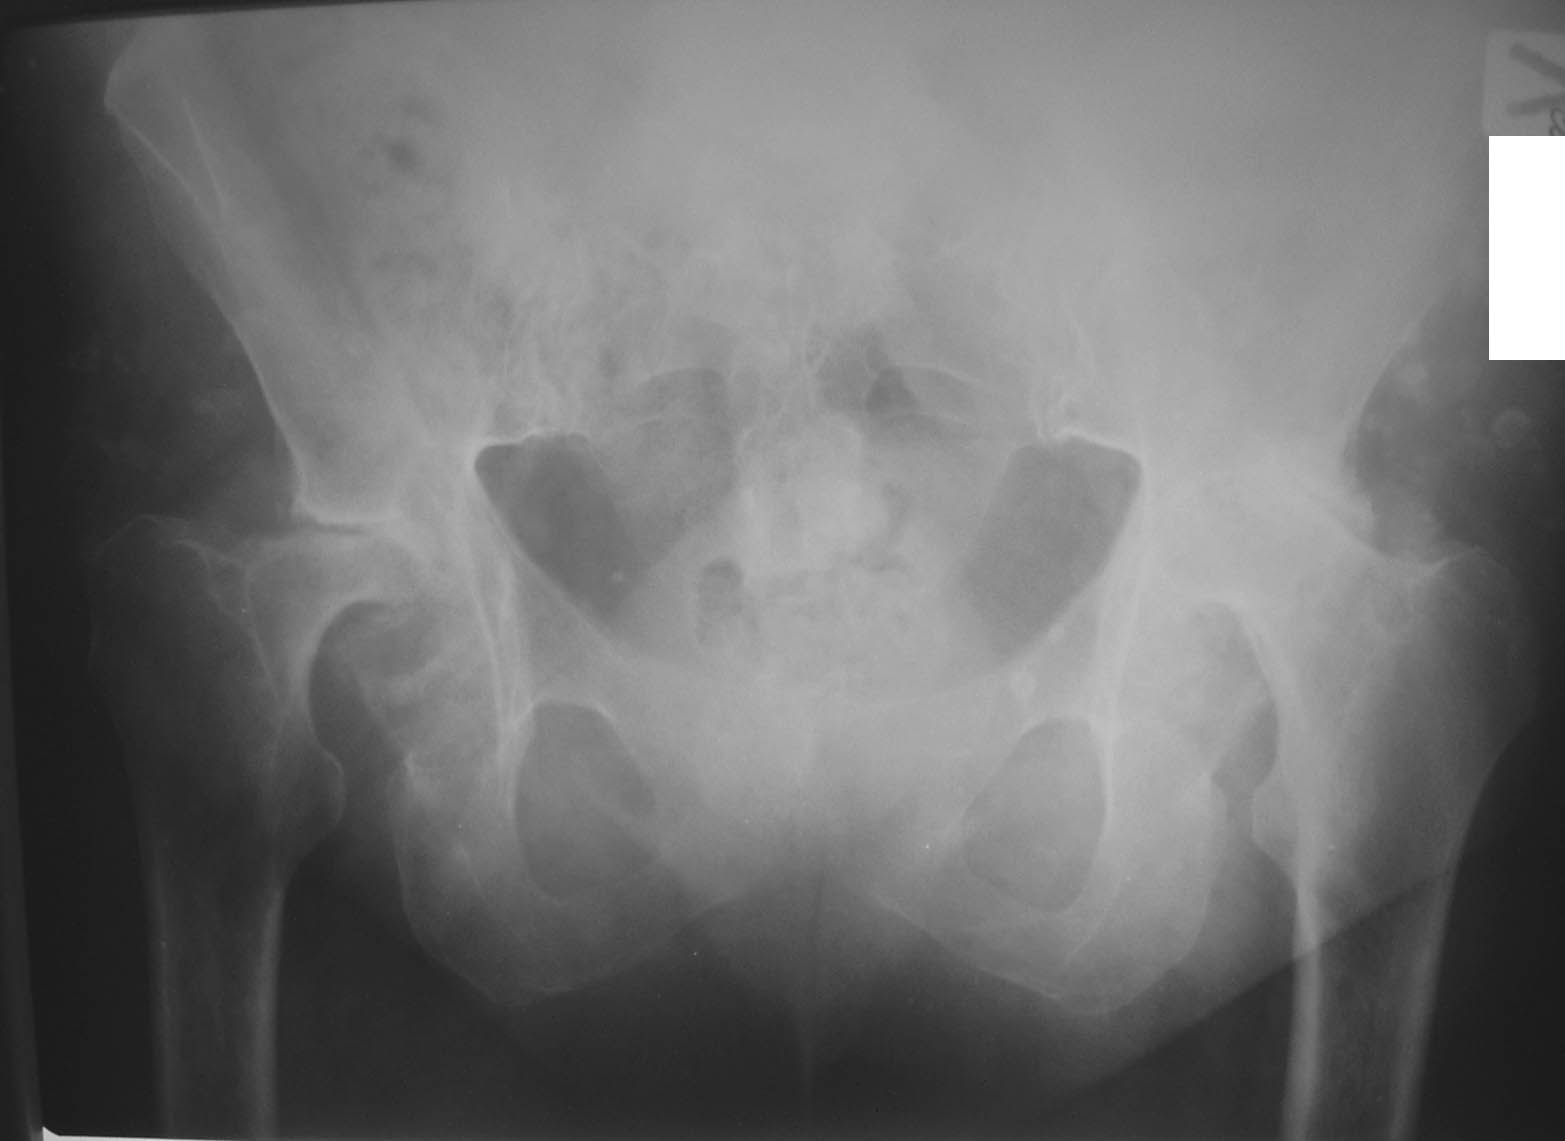

Пациентка С., женщина, 50 лет. Ревматоидный полиартрит. Двусторонний

ревматоидный артрит тазобедренных суставов.инвалид 1-й гркппы. Принимает

гормоны. Вопрос: с учетом возраста и состояния костной ткани - цементную

или бесцементную технологию эндопротезирования выбрать?